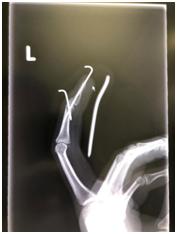

值得一提的是,本次手术是在手指局麻下进行,所以手术时的各种声音都可以听得到,而且一直照着X光进行手术,所以钢钉进去的样子是可以亲眼看到的。

手术时间大概1个小时,用了两条钢针。手术结束后手指稍微有一点疼痛感。因为医生技术好,就没有想像的那么痛了。